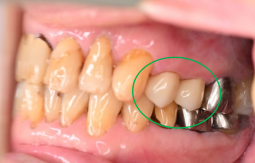

女性 Yさん 60代 (オールセラミック冠)

主訴

以前治療した右下の犬歯が、虫歯になり色が変わってきているので、治したい。

治療内容

根管治療をし、オールセラミック冠を被せました。

所感

神経が取り除かれ、歯自体が変色し、虫歯になっていました。根管治療をし、ファイバーコアを入れ、オールセラミック冠を被せました。

オールセラミック冠1本(失活歯):¥104,500(税込)

Before

After